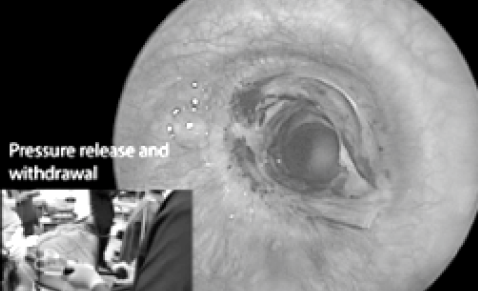

Single Stage Airway Balloon Dilatation for Laryngotracheal Stenosis

Sanchita Kalita, Biswajit Gogoi, Gautam Khaund